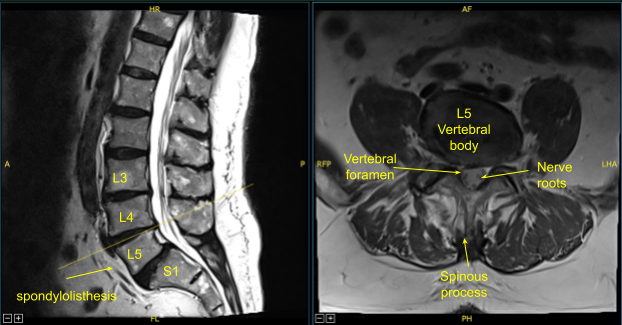

A patient presented to our clinic with signs and symptoms of lumbar spondylolysis, spondylolisthesis and spondylotic radiculopathy. Having failed conservative treatment measures, surgery was offered and recommended to decompress and stabilize the lumbar spine.

Sagittal View Axial View